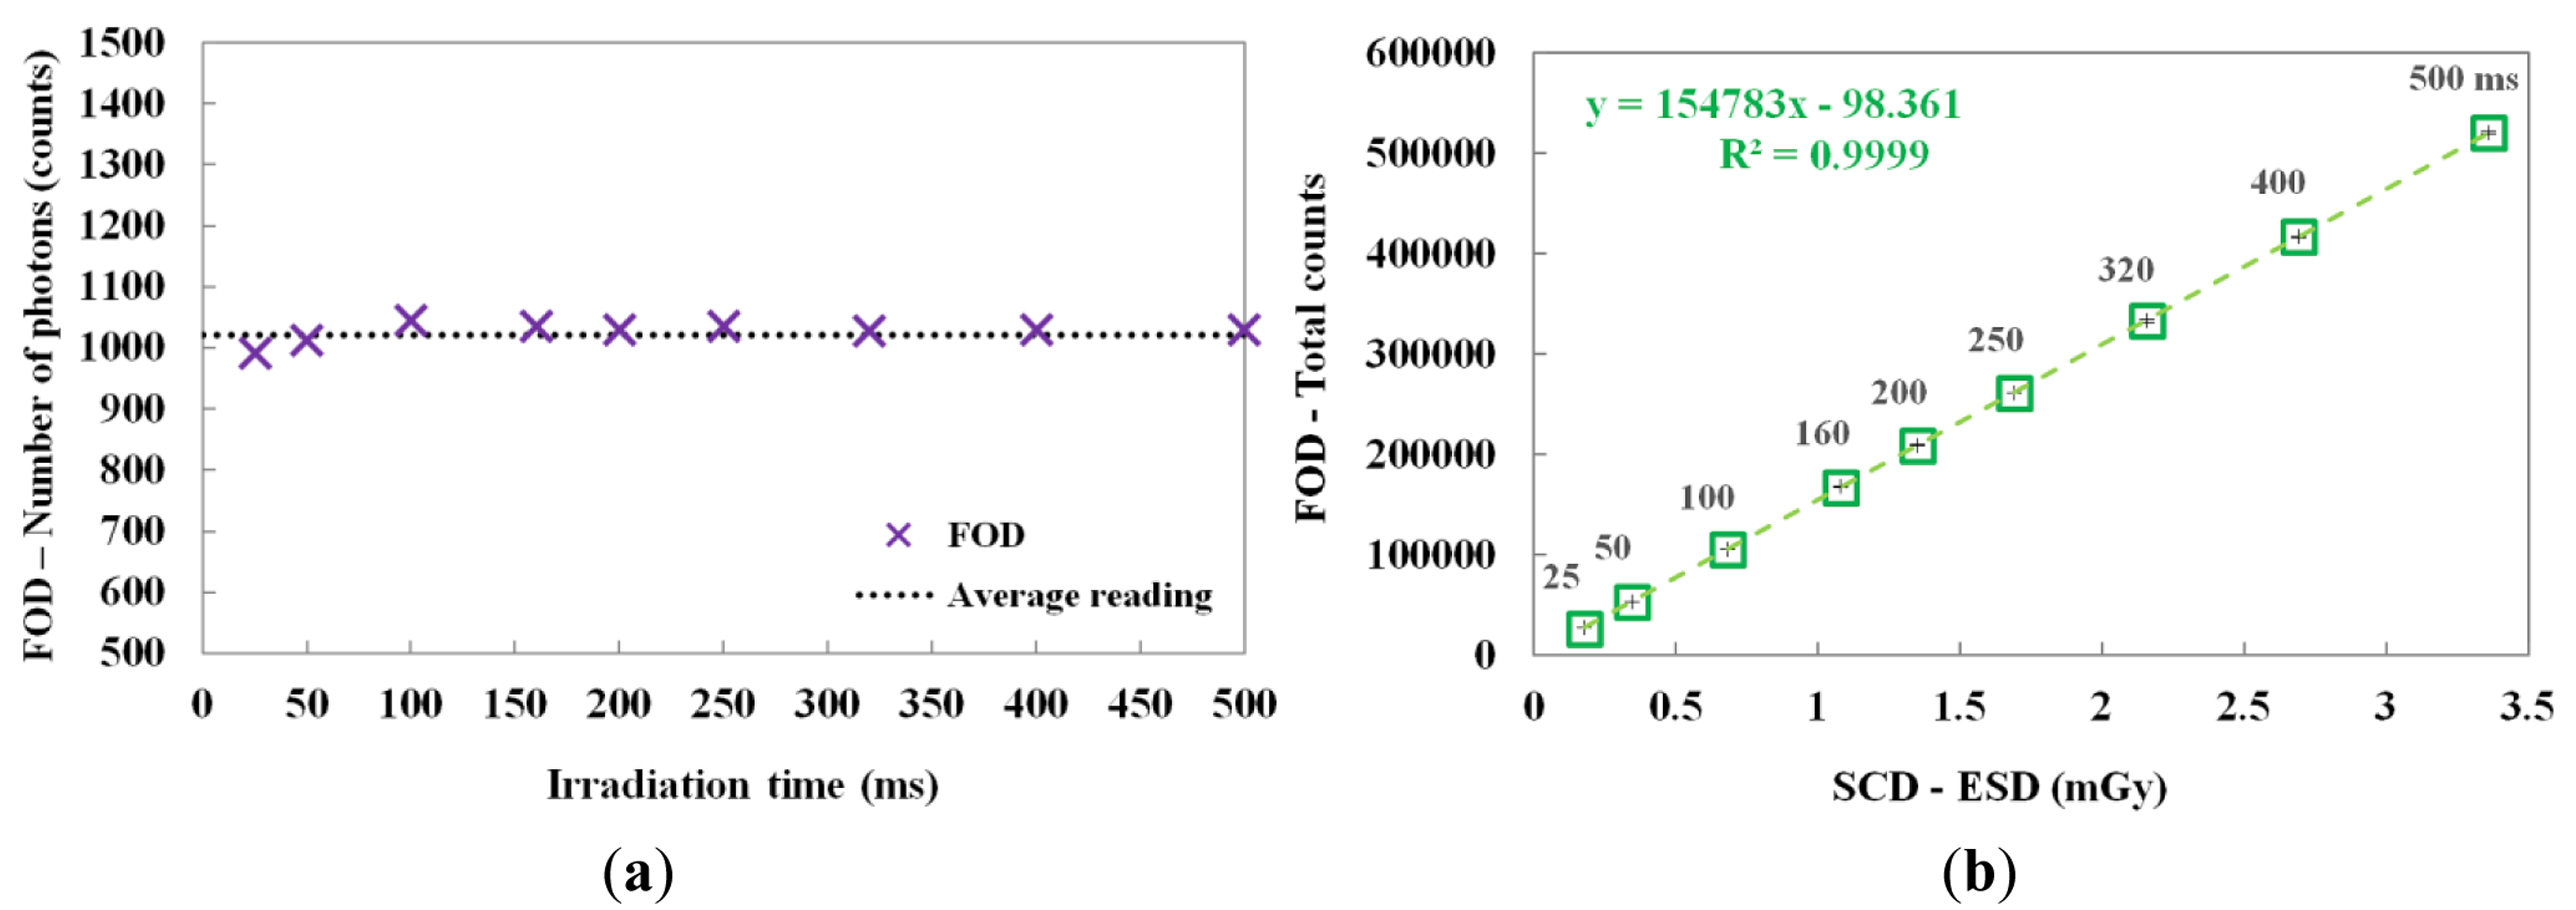

By changing the irradiation time, the scintillating light and the ESD were also measured. In this test, the irradiation time of the X-ray beam was varied from 25 to 500 ms while the tube current was fixed at 50 mA. Figure 6a shows the number of scintillation photons measured by the FOD during X-ray irradiation. Although the irradiation time was increased from 25 to 500 ms, the number of detected scintillation photons was almost uniform; however, the total counts of the scintillating light increased linearly with increasing ESD due to the irradiation time, as shown in Figure 6b. The mathematical form of the linear fit line to the coefficient of determination is also presented in Figure 6b and R2 was found to be 0.9999.

3.4. Performance Evaluation of the FOD with Constant Current-Time Product